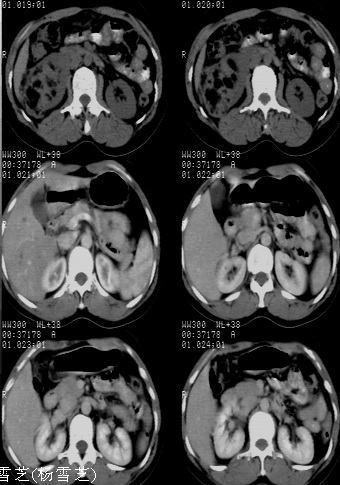

结果收到---右肾细胞癌;单就影像表现是应该首先考虑血管平滑肌脂肪瘤。

病理是有可能搞错不过可能性不大,不过这个确实不能报右肾细胞癌,真难

结果有疑问,什么级别的医院,会不会搞错了

该病理结果应该送高级别医院做病理会诊,否则会影响影像医师今后的判断。免疫组化结果也并未公布,结果非常可疑。应进一步证实。